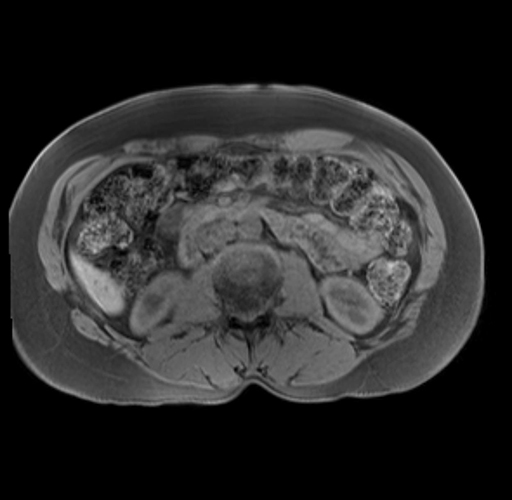

Imaging Analysis

Look through the patient's CT scan to identify any areas of concern for the necessary procedure.

Based on your CT findings, which issue(s) are present and would give reason for "planned slowing down moment(s)" in this case?